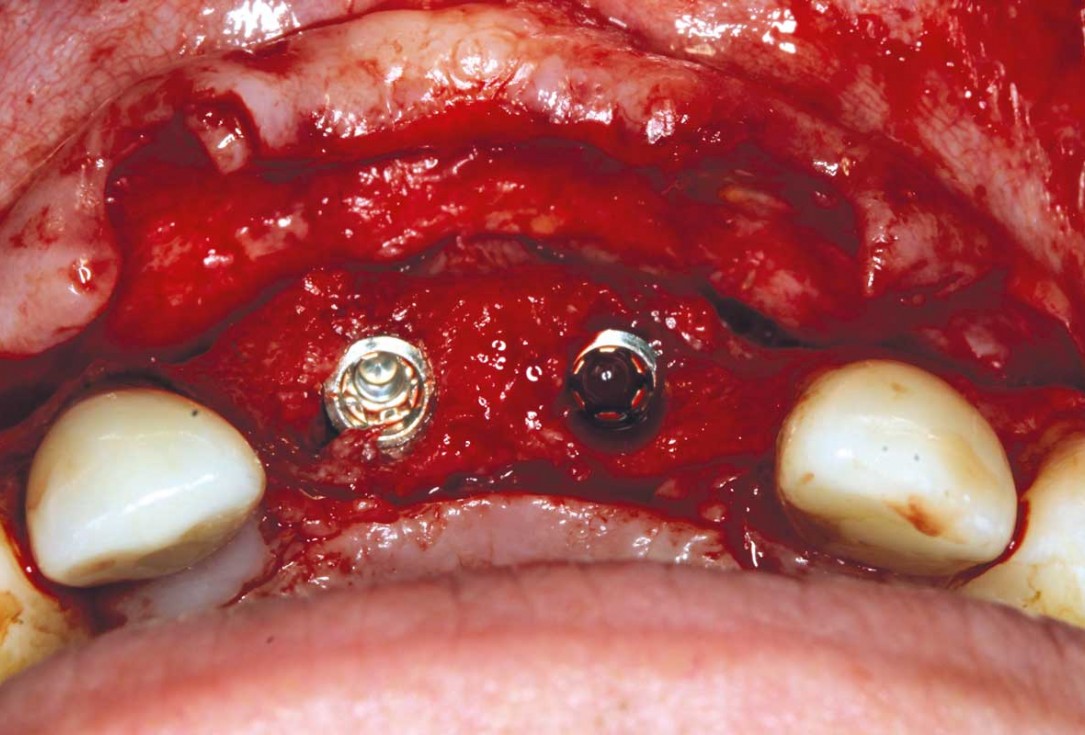

13/26 - Re-entry after 6 months

Ridge augmentation in the maxilla with maxgraft® bonebuilder in the aesthetic zone - Dr. M. Kristensen